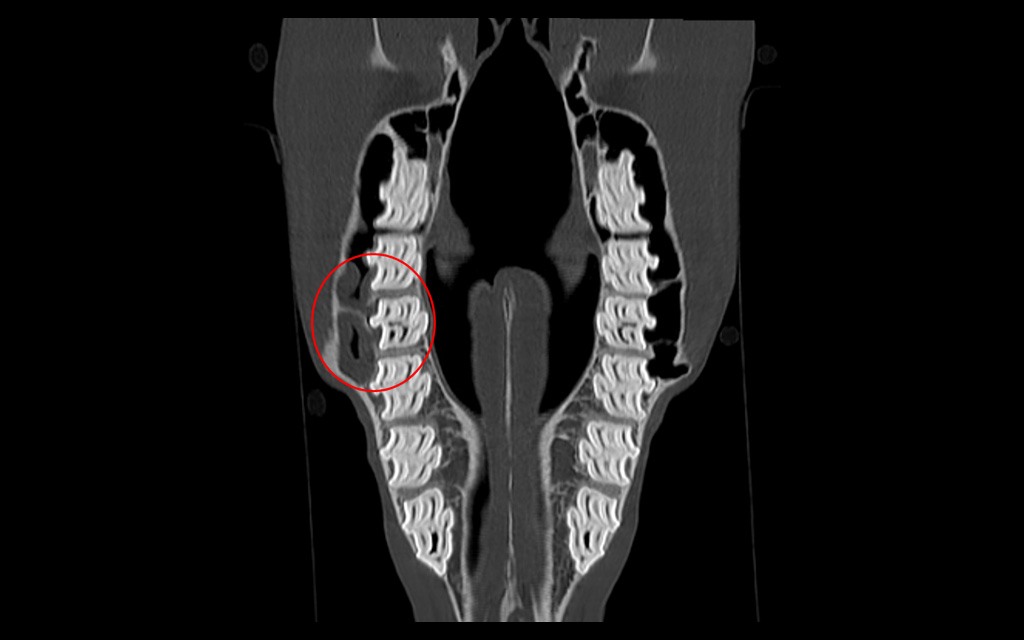

Bone window, coronal image, apical infection tooth 109, buccal wall discontinuity, gas inclusions, sinus involvement

Apical infection of tooth 109 with secondary sinusitis.

Radiographs showed abnormal pulp horns, an occlusal fissure, root shortening, and alveolar sclerosis, while CT revealed mucosal thickening in the maxillary sinuses, buccal wall discontinuity, and gas inclusions in the periodontal space and pulp chamber.